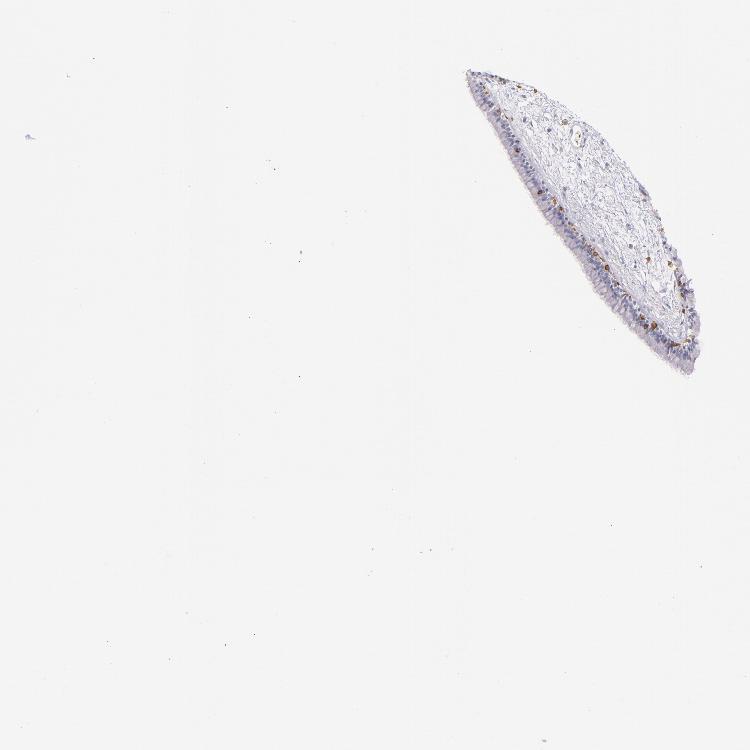

TISSUE PRIMARY DATA NASOPHARYNX Show tissue menu

NASOPHARYNX - Antibody stainingi

Antibody staining in the annotated cell types in the current human tissue is reported as not detected, low, medium, or high, based on conventional immunohistochemistry profiling in selected tissues. This score is based on the combination of the staining intensity and fraction of stained cells.

Each image is clickable and will lead to virtual microscopy that enables deeper exploration of all samples and also displays staining intensity scores, fraction scores and subcellular localization as well as patient and tissue information for each sample.

Antibody HPA011157Antibody CAB002223Antibody CAB012978Antibody CAB079960

Respiratory epithelial cells Not detectedNot detectedNot detectedNot detected